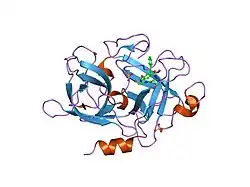

Urokinase is a 411-residue protein, consisting of three domains: the serine protease domain (consisting of residues 159–411), the kringle domain (consisting of residues 50-131), and the EGF-like domain (consisting of residues 1-49). The kringle domain and the serine protease domain are connected by an interdomain linker or connecting peptide (consisting of residues 132–158). Urokinase is synthesized as a zymogen form (prourokinase or single-chain urokinase), and is activated by proteolytic cleavage between Lys158 and Ile159. The two resulting chains are kept together by a disulfide bond between Cys148 and Cys279.[9]